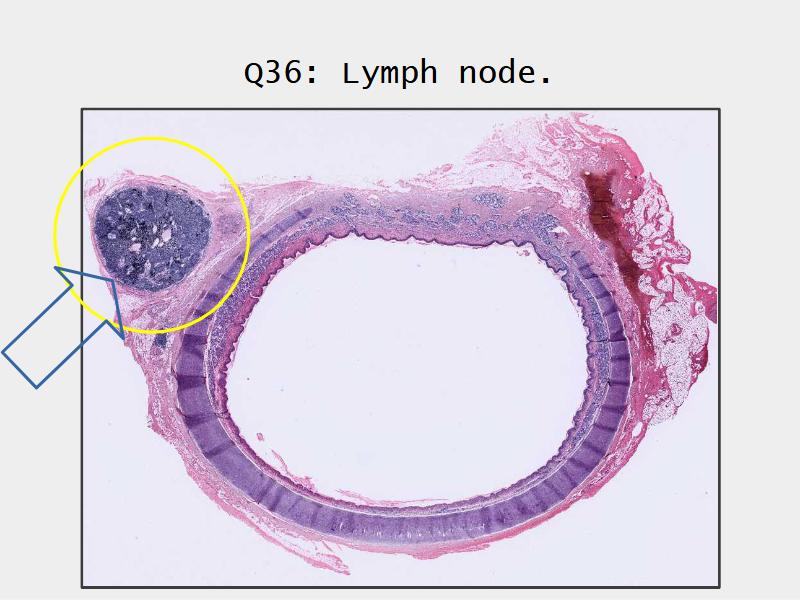

Slides: Respiratory System

- Slide 71: Nostril